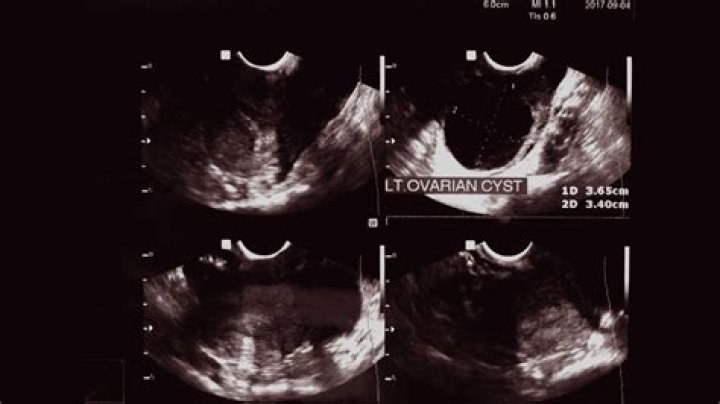

What size cyst needs surgery?

The size of a cyst directly corresponds to the rate at which they shrink. Most functional cysts are 2 inches in diameter or less and do not require surgery for removal. However, cysts that are larger than 4 centimeters in diameter will usually require surgery.

Most functional cysts are 2 to 5 centimeters (cm) (about 3/4 of an inch to 2 inches) in size. Ovulation happens when these cysts are around 2 to 3 cm in size. However, some may reach sizes of 8 to 12 cm (around 3 to 5 inches).